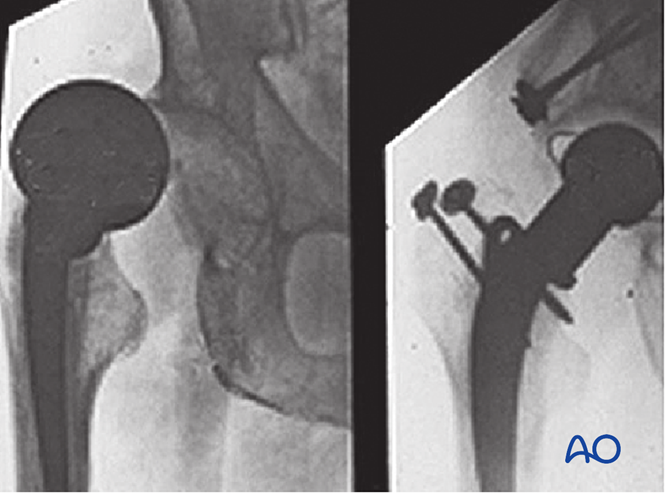

股骨颈骨折关节置换术后脱位是重要并发症。X线示例显示半髋假体脱位(左)及转为全髋假体修复(右):保留原股骨柄,移除股骨头假体,置入髋臼假体(辅以骨移植)后安装新头及衬垫。